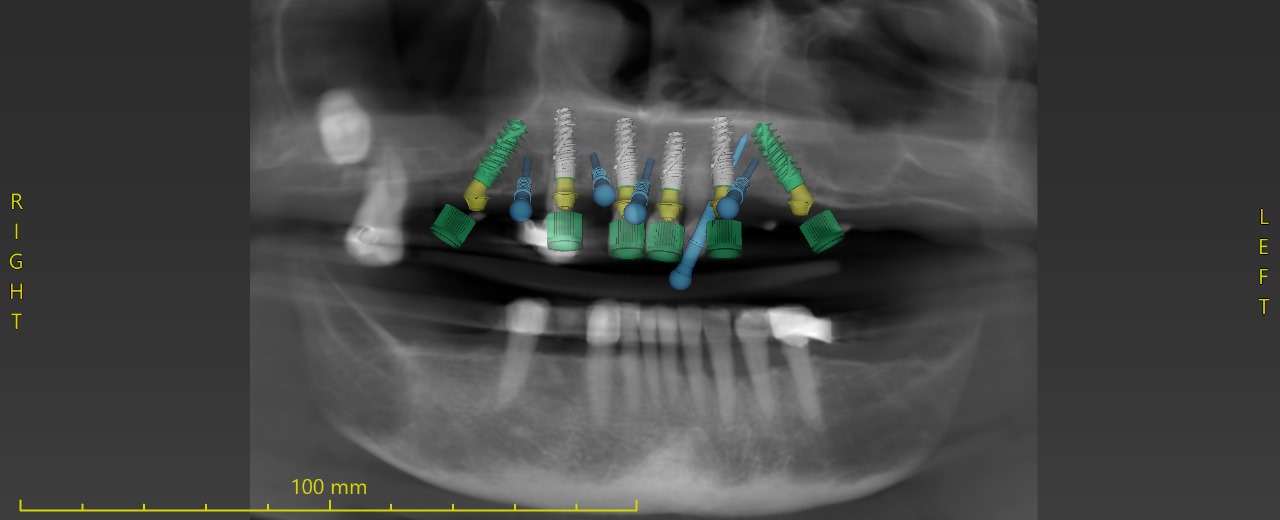

. Surgical guide design ( single sites to stackable full arch guide )

. Falcon guided system ( planning and giide designing )

Upper full arch